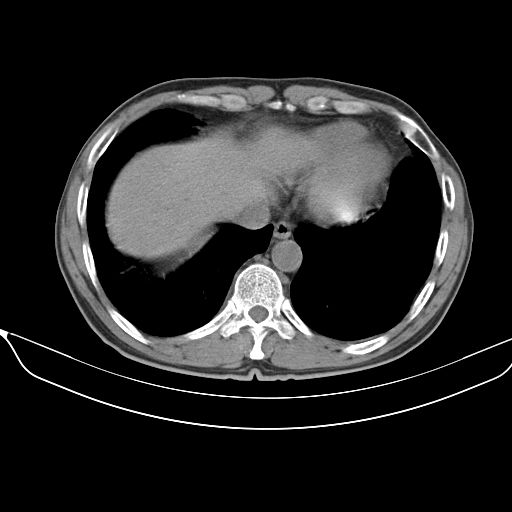

以下是引用心路寻觅在2010-3-1 10:23:00的发言:[br]1、考虑左肺上叶周围型肺癌[br]2、右上肺陈旧性病灶。[br][br][本贴已被 心路寻觅 于 2010-3-1 10:40:18 修改过]

以下是引用shuiyuan在2010-3-1 10:45:00的发言:[br]考虑左肺上叶中心型肺癌伴阻塞型炎症,邻近胸膜受侵。